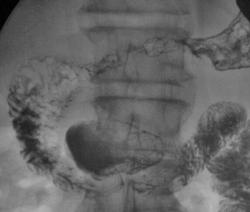

Осмелюсь предположить что в антральном отделе желудка есть рак,  инфильтративная форма.

На серии представленных вами снимков сделанных во время скопии, отмечается регидность участка и утолщение слизистой(отмечено стрелками), жалко только  что не была выведена петля 12п.к. в положении стоя, там бы мы увидели четко антральный отдел:

В антарльном отделе  не толко ригидность ,а стойкое циркулярное сужение.А вот по большой кривизне можно сказать ,что ригидность, хотя контур стенки ровный четкий, но при двойном контрастировании толком не расправился, да и перистальтика почти отсутствует

Протяженность процесса, учитывая зазубренность большой кривизны, надо думать была значительная?

Надо думать, что в антральном отделе, по большой кривизне, имела место быть "чашеподобная" карцинома, со значительным изъязвлением?